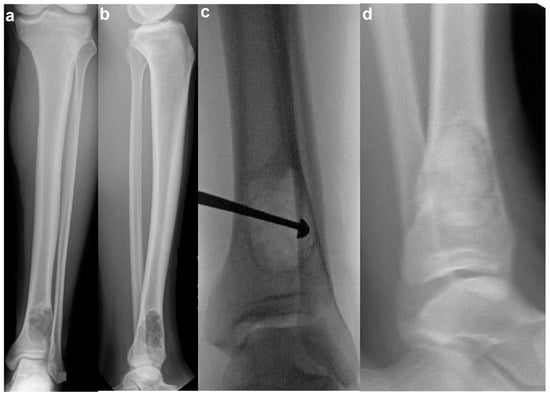

- Curettage and Bone Grafting: This is by far the most performed procedure. After curettage, the cavity is filled with autograft, allograft, or synthetic bone substitute [32]. While autograft is theoretically biologically superior, the donor site morbidity makes allograft the most used graft choice. In addition, the relatively high success rate and low risk of recurrence make the risks of an additional incision with autograft prohibitive. Synthetic substitutes such as calcium sulfate and calcium phosphate can provide structural support to allow earlier weight bearing. Again, the risks of cementation, in the setting of a benign disease with good operative results, make this a less common choice. Adjuvants are typically not used in the curettage stage for NOFs, as they are in giant cell tumors of bone or aneurysmal bone cysts. NOFs are not locally aggressive, and the use of phenol or argon beam coagulation is not typically indicated to reduce recurrence. Phenol and argon have a risk of local tissue damage, making them uncommonly used in the setting of NOFs. Figure 5 demonstrates pre-, intra-, and post-operative radiographic images of a 17-year-old boy with a large symptomatic distal tibia NOF who underwent a curettage and bone grafting procedure.